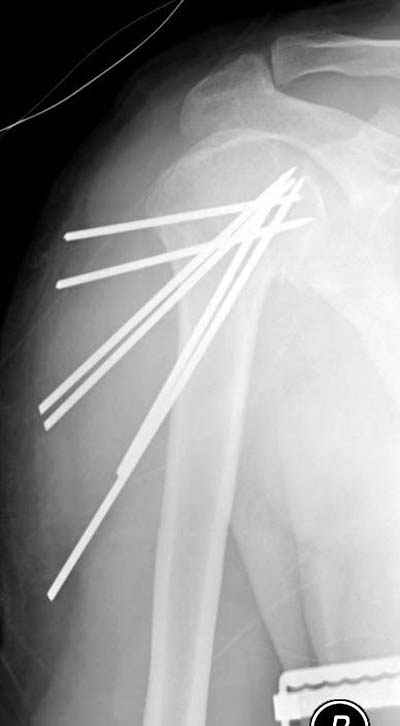

Спасибо за участие в дискуссии -перелом шейки плеча, для себя я прояснил многие технические моменты...

Посылаю послеоперационные Рг граммы.

Поздравляю, получилось просто замечательно. Если можно, расскажи чуть подробнее, как делали - как вправляли, как вводили спицы, поворачивали ли их?

|

Спасибо за поздравления:-))

Я и сам доволен результатом. В предпоследнем письме я кратко описал ход операции - закрыто репонировать не удалось( 2 недели с момента травмы и 1 неделя после неудачной репозиции) после удаления пучков спиц, пришлось сделать - 2см разрез на уровне перелома и с помощью периостального элеватора (золотое правило механики) *одеть* головку на дистальный отломок.

Спицы проводил через старые отверстия, вращая пучок импактором- направителем при его введении в головку.